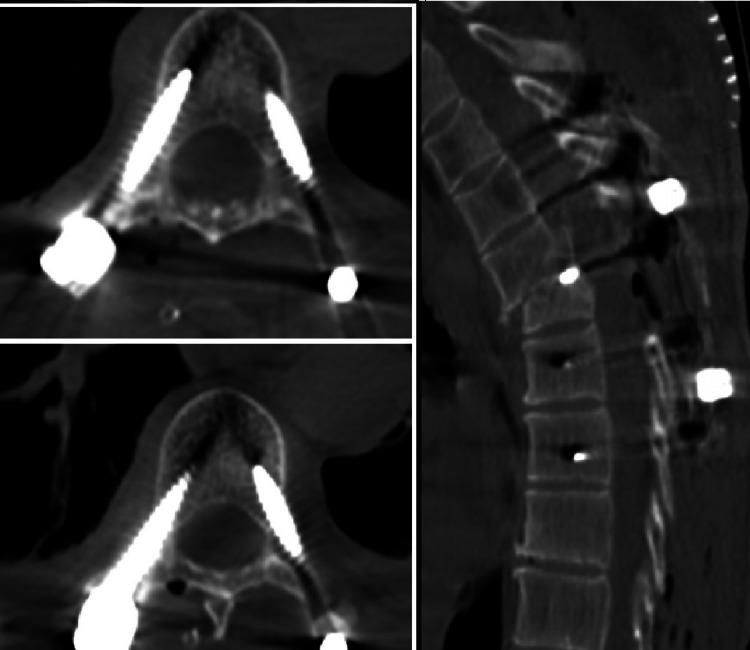

Background This study aims to compare the clinical results of patients with upper thoracic vertebral fractures treated with pedicle screw and posterior spinal fusion with preoperative surgical planning and 3-dimensional (3D) modeling and patients treated with freehand screws. Methods Fifty patients who underwent pedicle screw placement with a diagnosis of upper thoracic fracture between June 2018 and October 2020 were included in our study. Pedicle screws were used in 25 patients (group 1) after the planning was completed with the help of 3D preoperative printing and modeling. Pedicle screws were applied in 25 patients in the control group (group 2) using the freehand technique. Intraoperative bleeding amount, operation time, and correct screw placement data in both groups were recorded. Results The operation time was 134 ± 22 minutes for group 1 and 152 ± 38 minutes for group 2. The difference in operation times was found to be statistically significant (p < 0.05). Based on axial and sagittal reconstruction images, the accuracy rate of pedicle screw placement (grades 0 and 1) in group I was 96.6% compared to 83.6% in group II. The minor perforation rate (grade 1, <2 mm) was 5.8% in group I compared to 11.8% in group II. The moderate perforation rate (grade 2, 2-4 mm) was 3.4% in group I compared to 14% in group II. The severe perforation rate (grade 3, >4 mm) was 2.3% in group II; however, misplaced screws were not associated with neurological deficits. The difference in overall accuracy rates between the two groups was significant (p < 0.05). Conclusions For 3D models of upper thoracic pedicle screw insertion, guide plates can be produced inexpensively and individually. It provides a new method for the accurate placement of upper thoracic pedicle screws with high accuracy and secure use in screw insertion.

背景 本研究旨在比较采用术前手术规划和三维(3D)建模进行椎弓根螺钉及后路脊柱融合术治疗的上胸椎骨折患者与徒手置入螺钉治疗的患者的临床结果。方法 纳入2018年6月至2020年10月期间诊断为上胸椎骨折并接受椎弓根螺钉置入术的50例患者。25例患者(第1组)在术前3D打印和建模辅助完成规划后使用椎弓根螺钉。对照组(第2组)的25例患者采用徒手技术应用椎弓根螺钉。记录两组患者的术中出血量、手术时间和螺钉置入正确数据。结果 第1组的手术时间为134±22分钟,第2组为152±38分钟。发现手术时间差异具有统计学意义(p<0.05)。基于轴向和矢状面重建图像,第I组椎弓根螺钉置入准确率(0级和1级)为96.6%,而第II组为83.6%。第I组轻微穿孔率(1级,<2 mm)为5.8%,第II组为11.8%。第I组中度穿孔率(2级,2 - 4 mm)为3.4%,第II组为14%。第II组严重穿孔率(3级,>4 mm)为2.3%;然而,螺钉位置不当与神经功能缺损无关。两组总体准确率差异显著(p<0.05)。结论 对于上胸椎椎弓根螺钉置入的3D模型,可以廉价且个性化地制作导向板。它为上胸椎椎弓根螺钉的准确置入提供了一种新方法,在螺钉置入中具有高精度和安全使用性。